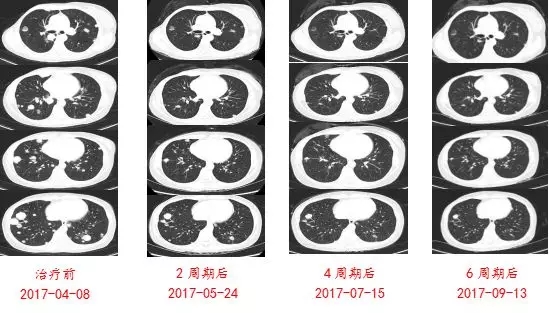

2017-04-11行“吉西他滨1000mg/m2 d1,8+阿帕替尼250mg 1/日”方案化疗6周期,疗效评估PR。

仔细阅片可以发现,该例患者首次复发时双肺多发转移,但在随后的在化疗中,胸部CT随访显示有的转移灶缩小,有的也出现了增大。这说明乳腺癌肺内不同部位的转移瘤存在治疗反应的差异,单个转移瘤活检,有可能不能反映所有转移瘤的生物学特性。所以,建议在治疗过程中,根据影像随访结果,在不同时间点,对治疗反应不佳的转移灶进行再次活检,有可能发现新的治疗靶点,为病人争取治疗的机会。